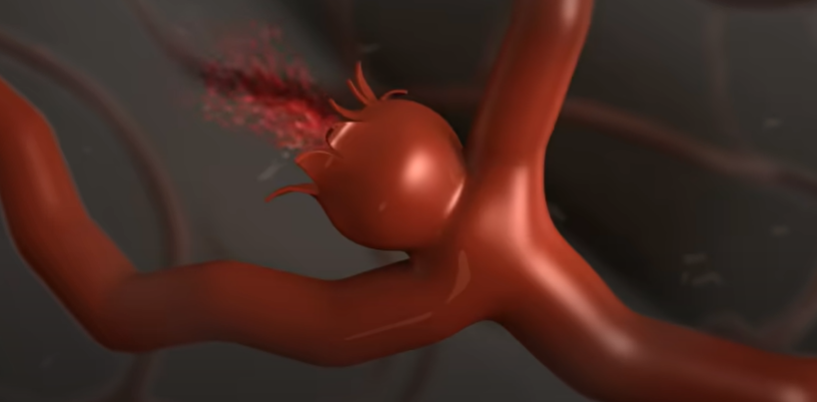

뇌동맥류

약해진 혈관 벽이 늘어나 마치 꽈리 모양으로 부풀어 오른 뇌동맥류는 터지는 순간 극심한 두통을 유발한다.

가장 위험한 게 뇌동맥류 파열에 의한 지주막하 출혈이다. 처음 출혈이 생기고 두통이 어느 정도 해소된 다음에는 환자가 마치 병이 나은 것처럼 생각하는데 만약 뇌동맥류가 터진 상태로 출혈이 멈추지 않으면 급사를 하게 된다.

뇌에 있는 동맥은 지주막하 공간이라는 뇌척수액이 가득 차 있는 곳에 있어서 마치 물에 동맥이 떠 있는 형태이다. 그곳에 있는 동맥류에 꽈리가 생겨서 파열되면 뇌 전체로 피가 퍼지기에 순식간에 뇌압을 상승시킨다. 뇌동맥류가 터지는 정도에 따라서 임상적으로 등급을 나누는데 한두 시간 정도 참을 수 있을 정도의 가벼운 두통부터 급사하는 정도까지, 출혈량이나 파열 정도에 따라 다양한 임상 증상이 생긴다.

목덜미에서 머리까지 아프기 때문에 '고혈압인가? 목 디스크인가?' 생각하는 경향이 있다. 그것도 어느 순간이 지나면 특징적 통증이 없어지고 약한 통증만 있어 구별을 잘하지 못하는데, 뇌동맥류가 파열돼서 가벼운 뇌 지주막하 출혈이 발생해도 두통이 특정 시점에 갑자기 생긴다. 이것이 매우 중요하다. 또한, 급작스럽고 평생 경험해보지 못한 정도의 굉장히 심한 두통이 오게 된다. 망치로 뒤통수를 세게 때리는 정도로 심한 두통이 갑작스럽게 오는 것이 특징이다.

뇌동맥류 증상, 형태

아래 사진의 특정 환자의 경우, 모두 6개의 뇌동맥류가 자리 잡고 있었다. 뇌동맥류는 터지기 전에는 별다른 증상이 없지만 크기가 클 경우 두통을 일으키기도 한다.

뇌동맥류의 크기가 가장 중요하다. 과거에는 10mm 이상의 뇌동맥류를 큰 동맥류라 했는데, 지금은 가장 긴 직경이 7mm 이상 되는 크기면 위험하다고 한다. 또한, 모양도 중요한데 밋밋하고 평평하게 생긴 뇌동맥류는 파열 위험성이 적으나, 매끈한 표면이 아닌 불룩한 형태의 울퉁불퉁한 형태나 뾰족한 뇌동맥류는 위험할 수 있다. 혈압이 높거나, 흠 연하는 경우, 여성이나 고령의 환자는 뇌동맥류가 커질 확률이 크다.